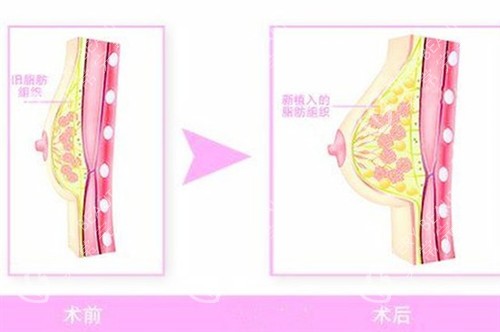

麻醉生效后,首先在预定位置(通常为乳晕缘或乳房下皱襞)做长约4-5cm的切口,然后在内窥镜引导下精细剥离胸大肌后间隙或双平面空间,这一步骤对术后假体的稳定性和手感至关重要。

腔隙剥离完成后,会植入经过严格消毒的假体,并在内窥镜下检查假体位置是否对称、边缘是否平整。

确认无误后,逐层缝合切口,通常使用可吸收缝线以减少疤痕。手术结束后,会为顾客穿戴专用的术后塑身衣,帮助固定假体位置并减轻肿胀。